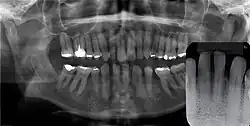

Gingival cyst of adult (arrow)

Panoramal radiograph of GCA. Inset: no evidence of bone involvement.

Gingival cyst of adult is a rare condition. The incidence is less than 0.5%. It is formed from the rests of dental lamina.[11] It is found in the soft tissues on the buccal and labial portions of the jaw. It usually occurs on the facial gingiva as a single small flesh colored swelling, sometimes with a bluish hue due to the cystic fluid. Sometimes, it may occur in cluster, either unilaterally or bilaterally or on the lingual surface of the alveolar process. It is most commonly seen in the canine and premolar regions of the mandible, and are sometimes confused with lateral periodontal cysts.[12] It is not normally problematic, but when it grows larger, it can cause some discomfort. It can be removed by simple surgical excision. They are developed late in life, generally up to the sixth decade of age.[1]